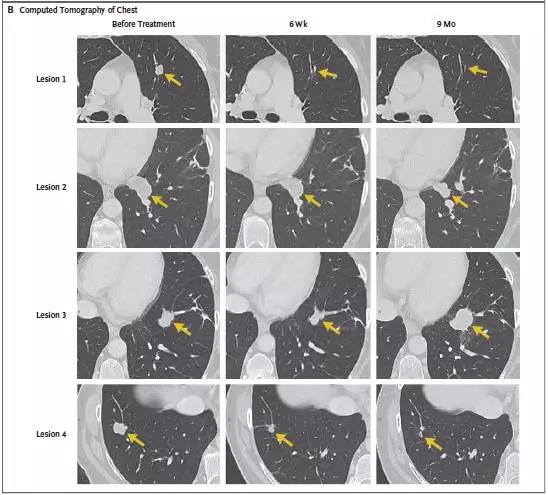

转移性结直肠癌患者肿瘤患者经过TIL细胞疗法治疗后,7个肺部的转移灶在几周后都变小乃至消失!